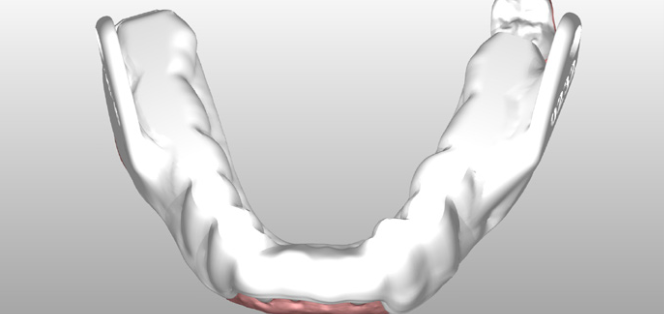

The full arch scans were exported to ResMed, where the 3D model was aligned with a virtual articulator and the Narval CC appliance designed using a completely digital workflow — no physical models, no alginate, no stone.

On fitting day, the device was checked for retention, occlusion, TMJ comfort, connector mechanics, and protrusion accuracy. The fit was accurate and comfortable — reinforcing the benefits of a fully digital impression and design workflow over traditional methods.

A digital workflow produces better-fitting, better-tolerated appliances. Digital scanning captures multiple bite registrations accurately, eliminates the distortion risks of alginate, and enables a fully CAD/CAM-designed device that is smaller and more comfortable than traditionally made alternatives.